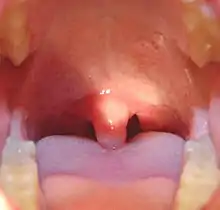

Palatine uvula

The palatine uvula, usually referred to as simply the uvula, is a conic projection from the back edge of the middle of the soft palate, composed of connective tissue containing a number of racemose glands, and some muscular fibers.[1][2] It also contains many serous glands, which produce thin saliva.[3]